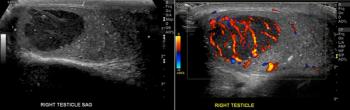

A 27-year-old man presents to his primary care physician, complaining of a palpable nodule in his right testicle. What is your diagnosis?